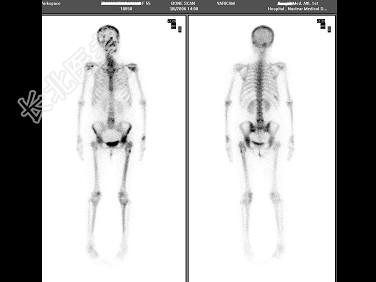

- 单项选择题女性,55岁, 左大腿上部疼痛3个月,X线片、CT均提示左股骨上段骨囊肿, 行全身骨显像如图,最可能诊断为 ( )

A、未见明显骨转移征象

B、右侧第9后肋、左股骨、左侧髋臼等骨转移改变

C、左股骨上段骨囊肿

D、右侧第9后肋、左股骨上段骨转移癌

E、以上都不是